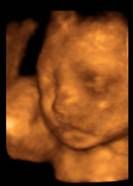

- USG narządu płciowego i ciąży -

certyfikaty Polskiego Towarzystwa Ultrasonografii i Fetal Medicine Foundation -

ultrasonografia 3D/4D kolorowy power angio Doppler

z możliwością nagrań na DVD i archiwizacji zdjęć na

czytnikach przenośnych

USG ciąży - rozszerzone (4 D)